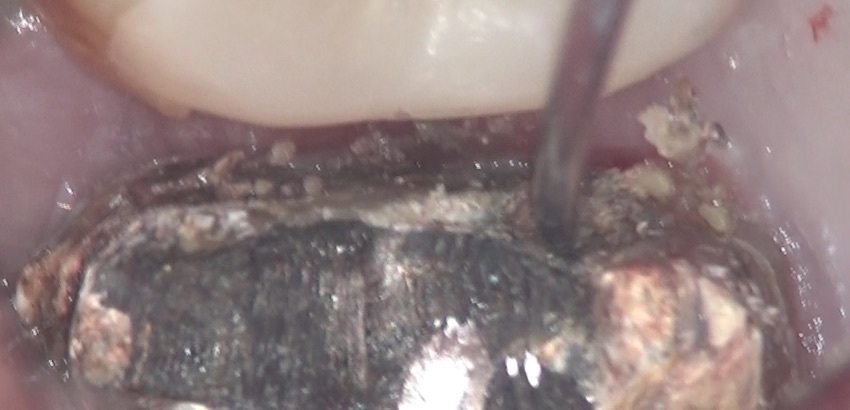

ここで、根尖性歯周炎に罹患している歯に装着されていた適合性の悪いクラウンを外した、その歯の状態を、写真で示します。

内部が汚くなっているのがわかると思います。

さらに、先の尖った器具で触ると、内部から感染性の歯質がボソボソ出てきました。

もうお分かりかと思いますが、それは、内部に細菌が侵入し、根尖に炎症も起きますよね。